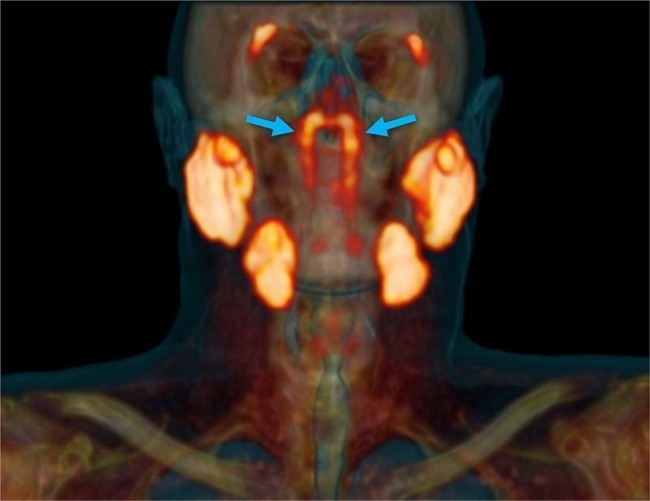

O novo órgão é um par de glândulas salivares localizado acima do palato e atrás do nariz e foi descoberto pelo Dr. Wouter Vougel e sua equipe do Instituto do Câncer da Holanda ao analisar tomografias cerebrais de alta resolução. Veja onde elas estão localizadas:

O par de glândulas foi nomeado como glândulas tubárias por conta delas estarem localizadas acima do chamado tórus tubário. O artigo publicado na revista Radiotherapy & Oncology ainda cita a importância da descoberta, que é inédita em mais de 300 anos de estudo da anatomia humana, pois as glândulas estão muito bem escondidas na estrutura craniana.

Imagem: Radiotherapy & Oncology

Para se ter uma ideia, os especialistas dizem que somente seria possível encontrá-las caso cientistas estivessem procurando exatamente por elas por meio de um exame de varredura PSMA PET/CT, que é geralmente empregado na procura de tumores.